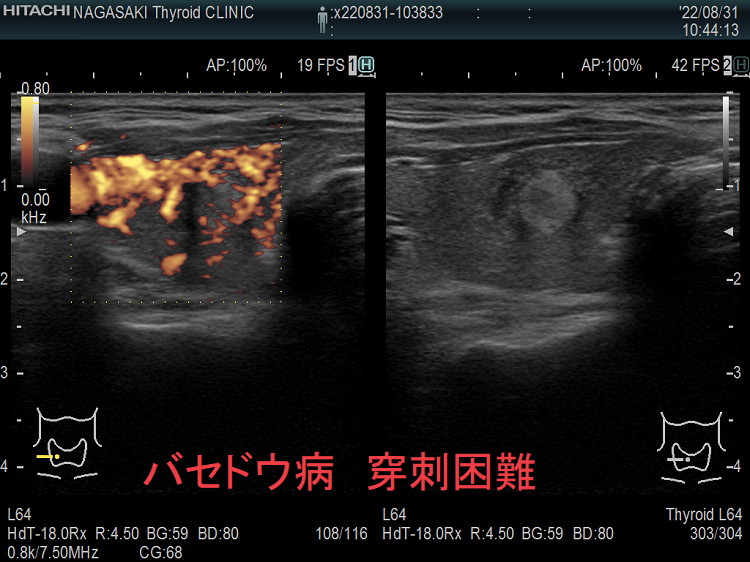

甲状腺穿刺細胞診の主な有害事象の一つは穿刺時出血、穿刺後出血;最悪、気道閉塞により窒息。注意しても唾を飲む方におこる。用手圧迫、再度、超音波エコー、造影CT、喉頭ファイバー行い出血・喉頭腫大を確認後入院。甲状腺機能亢進症/バセドウ病、TSH高値の重度甲状腺機能低下症は甲状腺内部血流が異常増加し穿刺で大出血の危険。甲状腺ホルモン正常化し血流低下を待つ。頚動脈に接する・連鎖して拍動する、下甲状腺動脈直下の小さな甲状腺腫瘍は穿刺難。甲状腺血管腫は何度穿刺細胞診しても血液成分のみで穿刺後出血の危険。最下甲状腺動脈穿刺で大出血。

穿刺細胞診するには、あまりにリスクが大きく、断念せざる得ない場合があります。たとえば、

甲状腺乳頭癌の可能性があるため、穿刺細胞診したくても、頚動脈や気管を刺してしまう危険を考えれば断念するのが正しいと思います。「退く勇気」も大切なのです。その代わり、甲状腺腫瘍が大きくならないか、腫瘍マーカーは上昇しないか、定期的に経過を見る必要があります。